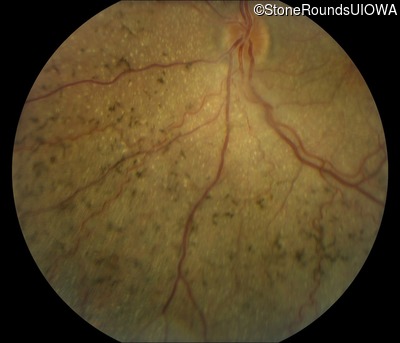

Fundus Photography - Left - 20/100 -2

Exemplar